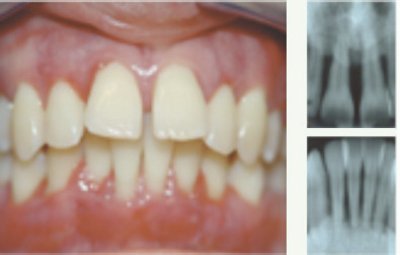

Weiterhin beunruhigend für die Experten ist jedoch die geringe Wahrnehmung dieser Erkrankung in der Bevölkerung: So glaubte nicht einmal die Hälfte der Betroffenen in einer Umfrage, dass sie an Zahnfl eischentzündungen leiden. Die Parodontitis ist eine Erkrankung, die durch Bakterien verursacht wird. Im Anfangsstadium der Erkrankung beginnt sich das Zahnfl eisch zu röten, reagiert empfi ndlich und blutet leicht. Schreitet die Erkrankung fort, bilden sich Zahnfl eischtaschen. Der dort entstehende Entzündungsprozess kann sich mit der Zeit auf den Zahnhalteapparat ausdehnen. Es kann zum Abbau von Bindegewebe und Knochen kommen und schließlich zum Zahnverlust führen. Mit dieser Erkrankung ist gelegentlich unangenehmer Mundgeruch verbunden. Für den Ausbruch der Erkrankung können jedoch nicht die Bakterien allein verantwortlich gemacht werden. Rauchen, eine erbliche Vorbelastung, Stress, schlechte Mundhygiene, Übergewicht, Hormonveränderungen, Zuckerkrankheit und Erkrankungen des Immunsystems sind zusätzliche Risikofaktoren, die den Ausbruch dieser Krankheit begünstigen.

Die Bakterien können weiter über die Blutbahn den gesamten Organismus befallen und Organe schädigen. Es gilt heute als gesichert, dass eine unbehandelte Parodontitis schwere Allgemeinkrankheiten wie z.B. Herzinfarkt, Schlaganfall oder Nierenbeckenentzündung begünstigen bzw. verursachen kann. Die Parodontitis ist eine heimtückische Erkrankung, die oft über lange Zeit schmerzlos und deshalb unbemerkt verläuft. Je früher man sie erkennt und behandelt, umso besser sind die Chancen einer Heilung. Die Paradontitis und die Schwere dieser Erkrankung werden vom Zahnarzt festgestellt, der eine dementsprechende Therapie einleitet. Diese Behandlung besteht in der konsequenten Beseitigung der Ursachen: Entfernung von Zahnstein und Zahnbelägen (z.B. durch professionelle Zahnreinigung in der Praxis) und Anleitung des Patienten zur richtigen Mundhygiene. Schlecht angepasste Kronen und Füllungen müssen ersetzt werden, bei Zahnfehlstellungen ist eine kiefernor thopädische Behandlung notwendig.